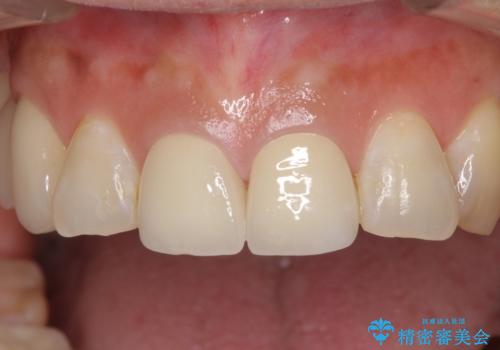

前歯2本を同時に処置したことにより、色合いも形態もバランスの取れた仕上がりとすることができました。

10年近く人にあまり見られないようにしていた前歯でしたが、人目を気にせず笑えるようになり、患者様には大変満足していただきました。